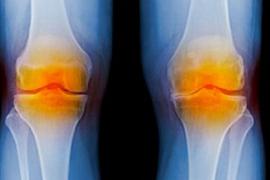

Bones and Joints

5 Knee Replacement Facts

Know your options for tackling knee pain, from joint replacement to nonsurgical treatments